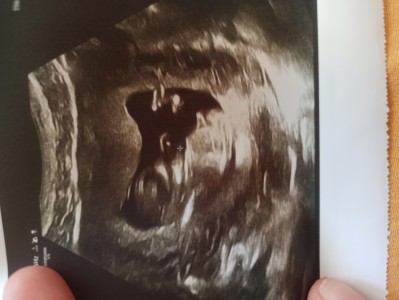

Cınsıyet resımlı

tahminde bulunur musunuz

Fark ettim daha çok küçük ama içimden erkek geçti nedense

12 haftalık biliyorum pek biçi belli değil ama merak

Net belli değil ama çıkıntı var sanki yani erkek gibi gördüm daha küçük ama yanıltır sizi zaten biraz daha sabredin inşallah belli olur gönlünüzce olur